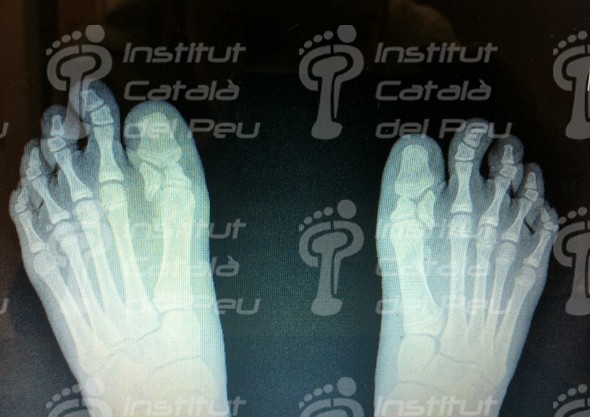

BIPARTITE PROXIMAL PHALANX

The bipartite proximal phalanx in an adolescent, sometimes is similar to a fracture, where you can think it may be caused by a lack of attachment in both bones, which can lead to a wrong diagnosis or even to splint unnecessarily the toe, or being operated surgically, bringing lesions in the growth cartilage with the total halt of the bone. Thus, we must consider the diagnosis very much and make radiographies in both feet to be able to compare and not to get wrong with a traumatism or Thiemann’s disease. In a nutshell, the best to distinguish is to watch carefully the radiography, the margines of the bone and in case it is clear, then it will be probably a bipartite bone.

The congenital malformation of first proximal phalanx is because of a lack of fusion or ossification of the primary and secondary nuclei of the phalanx, which this lack of union entails to produce the bipartite.